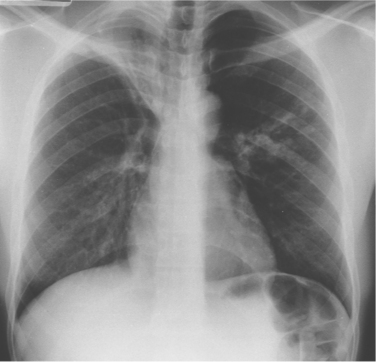

Complications associated with TB can include bronchopleural fistulae, esophagopleural fistulae, pleurisy with effusion, tuberculous pneumonia or laryngitis, and sudden lung atelectasis, indicating that a deep tuberculous cavity in the lung has perforated or created an opening into the pleural cavity, allowing air and infected material to flow to it (Fig. 15-6).

Figure 15-6 Segmental consolidation in tuberculous bronchopneumonia. The right upper lobe is grossly collapsed, scarred, and bronchiectatic. It had remained stable for many years until segmental nodular and linear consolidation appeared in the left mid zone, signaling reactivation. The segmental lesion was thought to be secondary to aspiration of bacteria from the right upper lobe. (From Grainger RG, Allison D: Grainger and Allison’s diagnostic radiology: a textbook of medical imaging, ed 4, Philadelphia, 2001, Churchill Livingstone. Used with permission.)